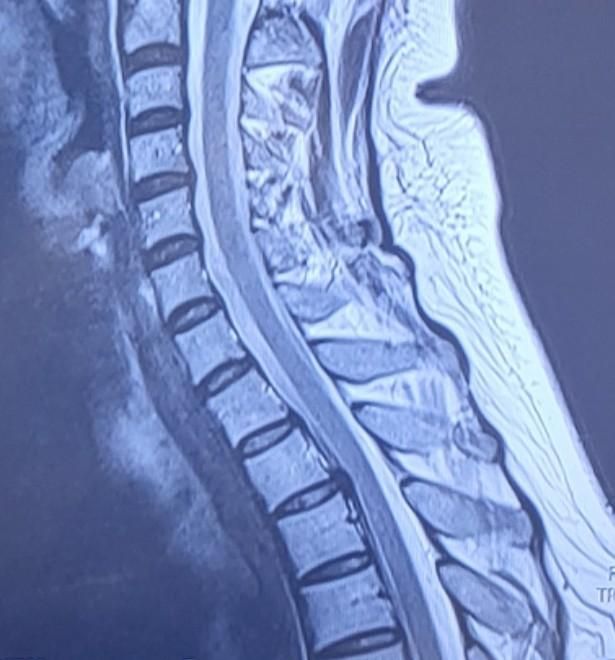

흉추 후종인대골화증 진단 받았습니다

흉추 2 3번 진단받았는데

• 1번 째 사진

흉추 2, 3번의 후종인대골화증(OPLL) 진단을 받았지만, 병원에서 약물 치료가 필요 없다고 한 것은 현재 신경을 심하게 압박하지 않거나 진행 속도가 느린 상태일 가능성이 큽니다. 일반적으로 흉추 2, 3번은 목이나 어깨보다는 상체 중심부(가슴, 등 쪽)와 관련된 신경을 담당하므로, 승모근과 날개뼈(견갑골) 쪽 통증과 직접적인 연관이 적을 수도 있어요.